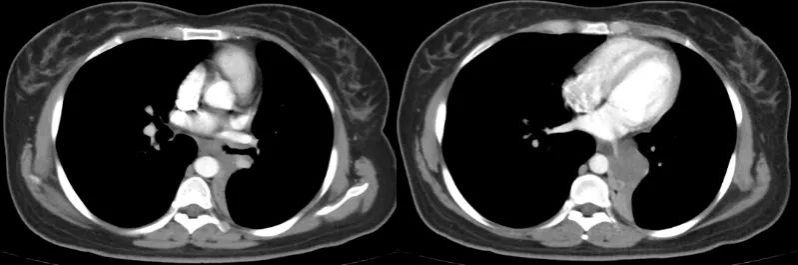

术前胸部CT

CT检查发现,耿女士的左肺支气管内有一个肿物,已经完全堵塞了左肺下叶支气管和部分左肺上叶支气管,雪上加霜的是,肿瘤还完全包绕关键的肺血管——左肺下叶静脉。医生为耿女士进一步完善了气管镜检查,发现在左主支气管开口下2-3cm处可见肿物,肿物沿着管腔延伸至下叶,取活检后病理明确为腺样囊腺癌。

经多学科MDT会诊,强光亮建议:“患者目前情况不乐观,根据肿瘤的生长部位,需要全肺切除才能保证肿瘤完整切除。但是肿瘤沿气管外侵很严重,下肺静脉完全被肿瘤包绕,可能侵犯心脏了!总体来说,手术可以尝试,但风险比较大。我们与心脏外科共同制定手术方案,同台手术,保证安全。”